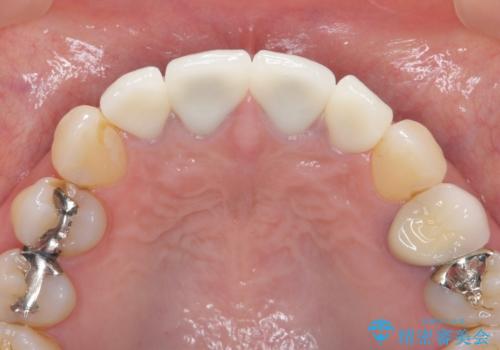

- 44万円(仮歯・ジルコニアクラウン×4)費用は治療当時の料金となります

金属を用いないジルコニアセラミッククラウンは透明感の再現性に優れ、審美性と自然な仕上がりの両立を期待することができます。